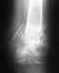

Re: Перелом руки со смещением (3 месяца)

послал Alexander Chelnokov 13 Октябрь 2010, 10:36

Прошло больше месяца. Есть смысл еще раз посмотреть на пациента и свежий снимок.